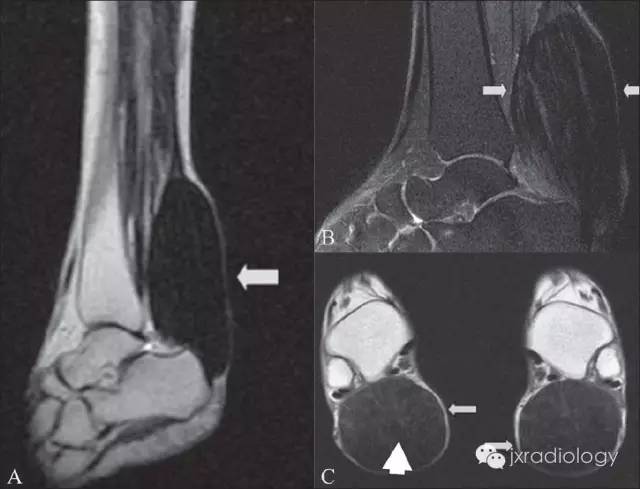

影像学表现:MRI典型病变的信号为跟腱明显梭形增粗 T1WI 像上呈顺跟腱长轴的类似肌肉的信号,表现为毛刷样改变,在 T2WI 像上也呈较低信号影,其内有斑点状短 T1 长 T2 较高信号影,T2WI 压脂像高信号区为低信号。CT:双侧跟腱部对称或单侧类梭形软组织肿块,向外膨隆,类似于肌肉密度,CT 值约 60~80Hu,与正常肌腱无法区分。